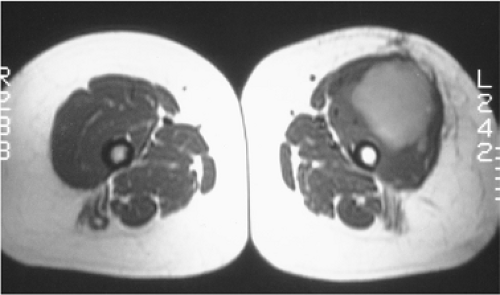

9e5a208ed129c1fe971350d197fcfb2c.gif

图-3放射治疗。轴位T1像显示一个恶性软组织肿块,股骨内为脂肪性骨髓。与对侧股骨内正常的低信号红骨髓进行比较。